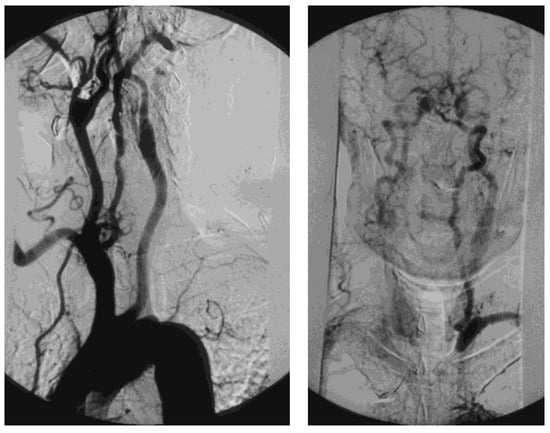

Figure 15. Arteriography showing occlusion of the left prevertebral subclavian artery at its origin (on the left): the late angiogram (on the right) demonstrates the blood flow inversion in the left vertebral artery, revascularizing the left subclavian artery after the occlusion, that is subclavian steal syndrome.

2.6. Prevertebral Subclavian Artery Stenosis (PSAS)

A tight atherosclerotic stenosis (or occlusion) at the origin of the subclavian artery before the onset of its first collateral branch, the vertebral artery, can cause a brain stem blood steal during homolateral upper limb efforts, in favor of the latter, through a blood flow inversion in the homolateral vertebral artery itself. This condition is known as subclavian steal syndrome (SSS), which can acutely give rise to dramatic vertebrobasilar symptoms such as vertigo and lipothymia up to syncope (Figure 15).